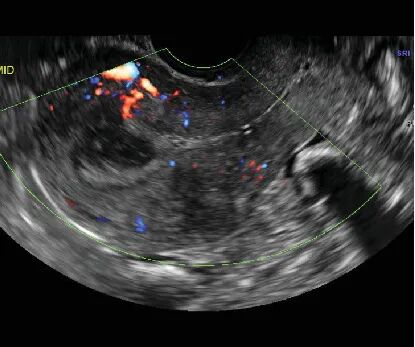

流产后复查超声,结果报告显示血流信号不丰富,不像典型的子宫动静脉畸形,这与之前的CT血管造影和临床病史产生了矛盾。

当宫腔压力降低时,它看得不清楚,这也解释了为什么怀孕时能发现,清宫后反而超声显示血流信号不丰富的原因了。

经阴道彩超是首选筛查工具,医生可以看到子宫里有一个富含血流信号的团块,多普勒技术能测到里面血流速度极快、阻力极低的特征,但本案例清宫手术后超声典型特征消失,可造成误诊。

实际临床中,有些小的子宫动静脉畸形血管团块在非孕期可能不明显,但怀孕后,由于全身和子宫血流量大增,它也会随之长大或变得更容易被检测到。